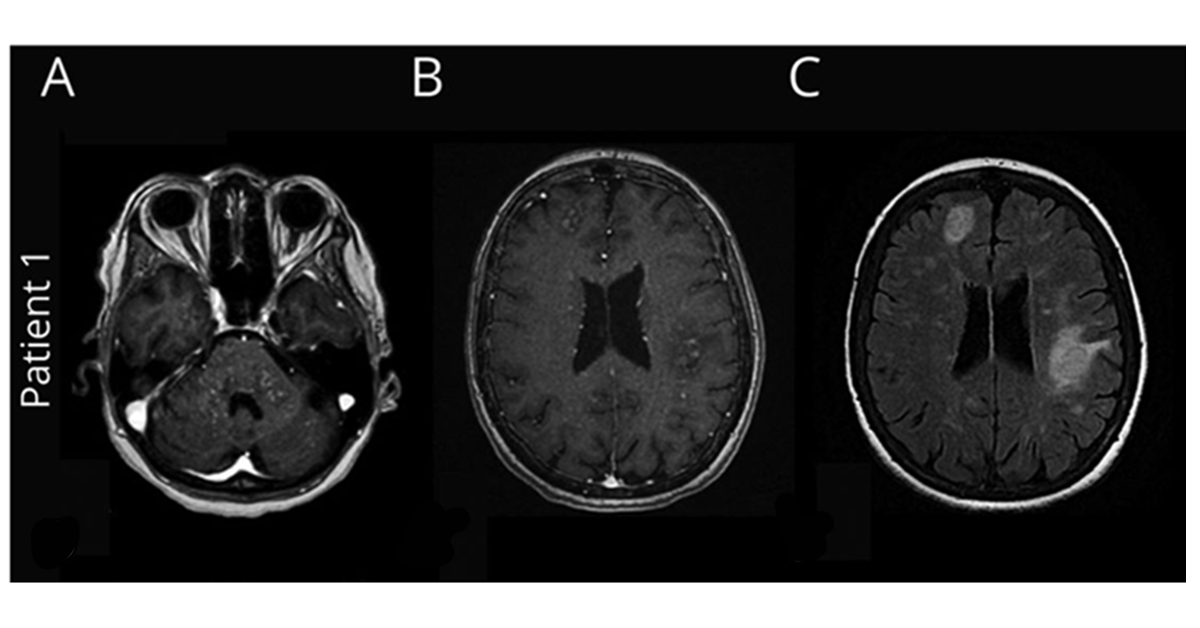

Clippers Syndrome - Https Www Thieme Connect De Products Ejournals Pdf 10 1055 A 0874 2106 Pdf - It affects both genders with possibly a minor male predominance.. Two new cases and literature. Diagnosis and management in pitt‐hopkins syndrome: The appearance of clippers on mri is fairly unique, characterized by multiple punctate, patchy and linear regions of contrast enhancement relatively confined to the pons 1 clippers syndrome. Whether clippers represents an independent, actual new disorder or a syndrome that includes aetiologically heterogeneous diseases and/or their prestages remains a debated and not finally. Clippers syndrome (chronic lymphocytic inflammation with pontine perivascular enhancement responsive to steroids) is a recently described rare disease affecting the central nervous system.

A clinically heterogeneous entity distinct from brody disease: Current concepts on pathogenesis and prevention brody syndrome: Metaanalysis for the evaluation of risk factors for carpal tunnel syndrome (cts) part ii. In addition, we also present a unique case of newly described autoimmune entity clippers syndrome. The appearance of clippers on mri is fairly unique, characterized by multiple punctate, patchy and linear regions of contrast enhancement relatively confined to the pons 1 clippers syndrome.

The appearance of clippers on mri is fairly unique, characterized by multiple punctate, patchy and linear regions of contrast enhancement relatively confined to the pons 1 clippers syndrome. Metaanalysis for the evaluation of risk factors for carpal tunnel syndrome (cts) part ii. Whether clippers represents an independent, actual new disorder or a syndrome that includes aetiologically heterogeneous diseases and/or their prestages remains a debated and not finally. Current concepts on pathogenesis and prevention brody syndrome: Clippers syndrome, brainstem, immunosuppressive therapy, corticosteroids. Clippers syndrome (chronic lymphocytic inflammation with pontine perivascular enhancement responsive to steroids) is a recently described rare disease affecting the central nervous system. A clinically heterogeneous entity distinct from brody disease: It affects both genders with possibly a minor male predominance. Diagnosis and management in pitt‐hopkins syndrome: Clippers syndrome can occur at any age, ranging from 15 to 85 years with a mean age around the fifth decade 2. In addition, we also present a unique case of newly described autoimmune entity clippers syndrome. Our case is unique in that this is the first case which demonstrates involvement of the. Becker p.m., jamieson a.o., brown w.d.

The appearance of clippers on mri is fairly unique, characterized by multiple punctate, patchy and linear regions of contrast enhancement relatively confined to the pons 1 clippers syndrome clippers. Becker p.m., jamieson a.o., brown w.d.